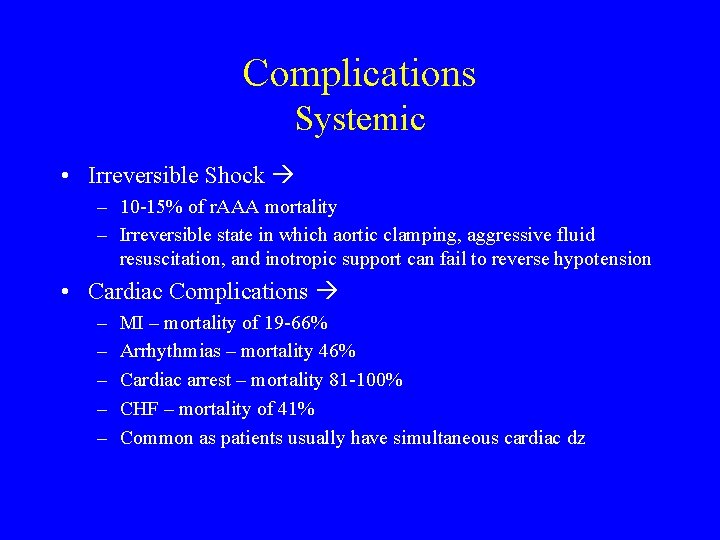

Complications Systemic • Irreversible Shock – 10 -15% of r. AAA mortality – Irreversible state in which aortic clamping, aggressive fluid resuscitation, and inotropic support can fail to reverse hypotension • Cardiac Complications – – – MI – mortality of 19 -66% Arrhythmias – mortality 46% Cardiac arrest – mortality 81 -100% CHF – mortality of 41% Common as patients usually have simultaneous cardiac dz